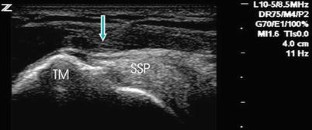

Abb. 4